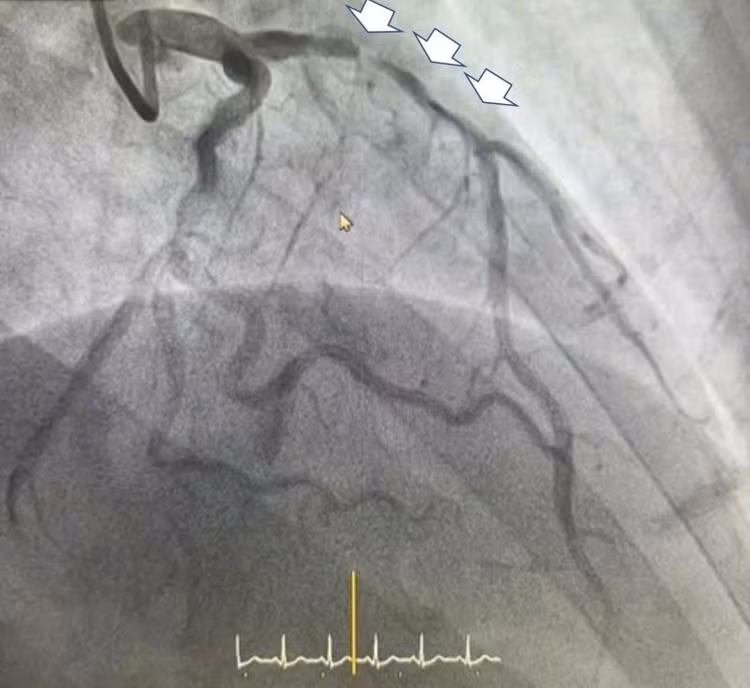

Sau can thiệp đặt Stent - Ảnh BVCC

Trên phim chụp chúng tôi ghi nhận còn một tổn thương hẹp nặng khác, mức độ hẹp lên tới 90% ở động mạch vành phải, tuy nhiên đánh giá tổn thương, dòng chảy và tình trạng bệnh nhân, ê kíp đã quyết định sẽ can thiệp thì hai trong thời gian nằm viện để đảm bảo an toàn cho người bệnh.

Với sự nhanh chóng nhưng rất thận trọng trong quá trình can thiệp, cả 2 lần đặt stent cho anh H. đều diễn ra thuận lợi. Kết quả chụp siêu âm trong lòng mạch IVUS cho thấy stent áp sát thành mạch, dòng chảy khơi thông tốt. Ngay sau can thiệp, bệnh nhân H không còn cảm thấy đau tức ngực như trước nữa.